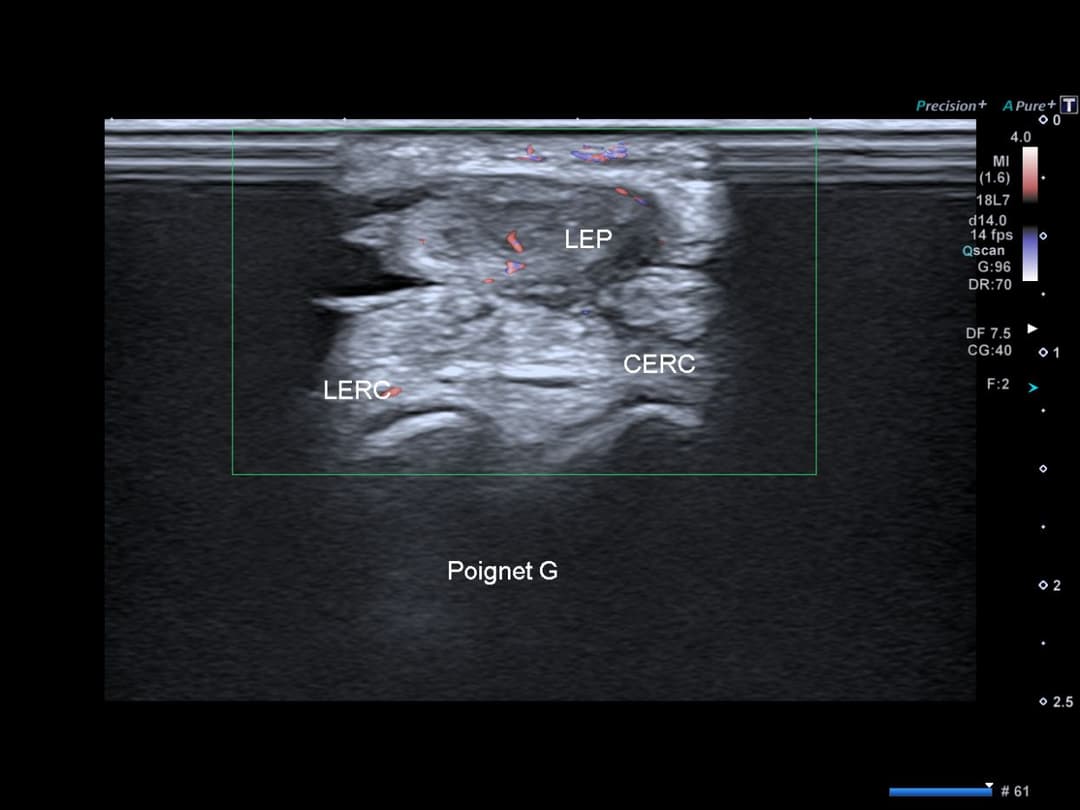

Epanchement filiforme dans la gaine de ce tendon et dans celle des extenseurs radiaux du carpe.

Désorganisation architecturale du tendon EPL au niveau du croisement avec le compartiments des extenseurs radiaux, qui présentent un épanchement dans leur gaine synoviale.